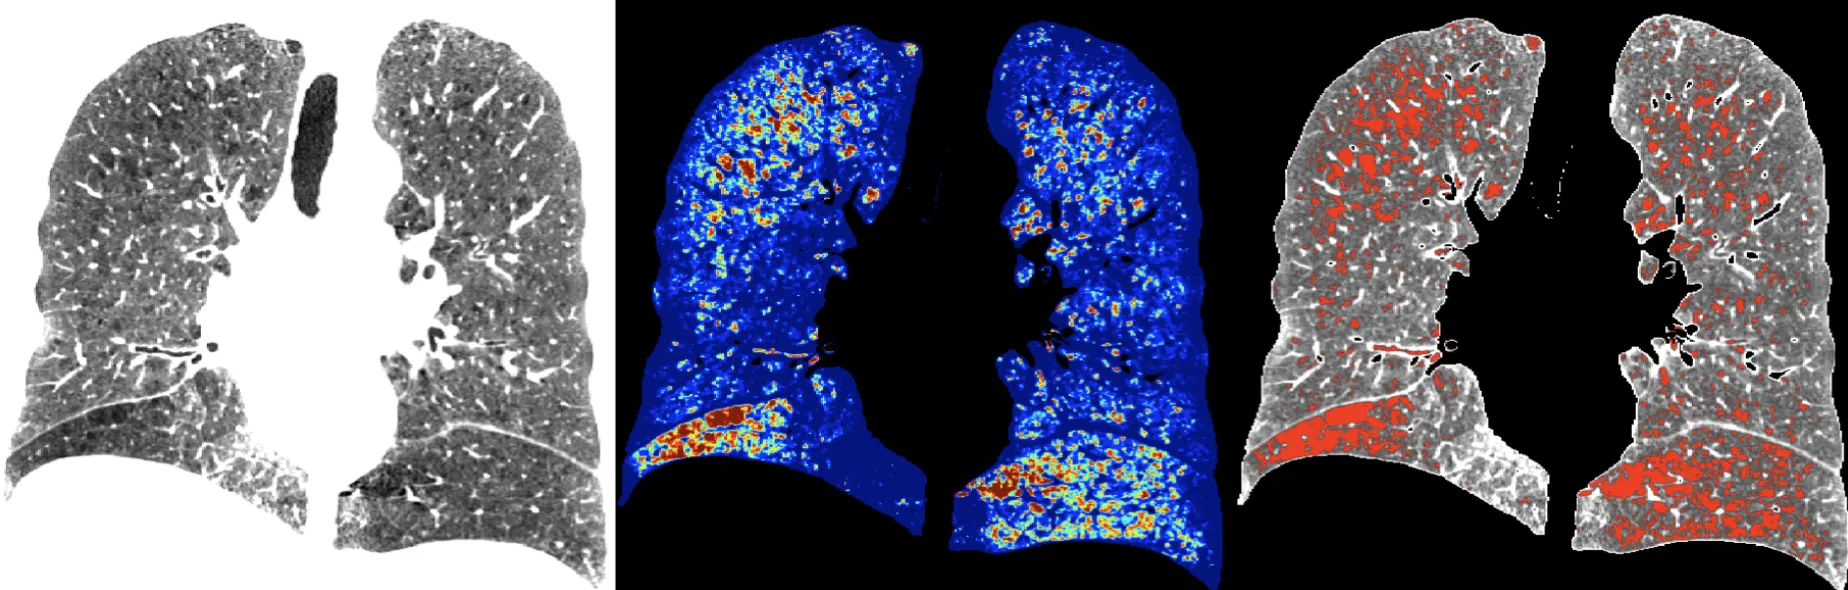

We have strong expertise in multiple methodological techniques, such as wavelet decomposition, speckle tracking, texture analysis, variational segmentation, parametric deformable models, and PET reconstructions. We deal with a wide range of imaging modalities, including 3D real-time echocardiography, lung computed tomography (CT), ultrasound, magnetic resonance imaging (MRI), and positron emission tomography (PET).

Adaptive quantification and subtyping of pulmonary emphysema from CT images

Funded by National Institutes of Health (NHLBI)1 R01

Period: 2012 -current

Short Info : Pulmonary emphysema is a condition involving alveolar wall destruction, contributing to chronic airflow limitation characteristic of chronic obstructive pulmonary disease (COPD). The processes underlying COPD are currently not well understood, even though the disease is a leading cause of morbidity and mortality worldwide.